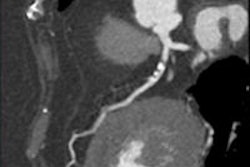

Radiologists from Maastricht University tested their new automated contrast injection device on a few hundred patients and compared the results with a control group that received a fixed contrast dose. Just by inputting patient weight before the scan, the investigators ended up with even opacification and several other benefits in the bargain.